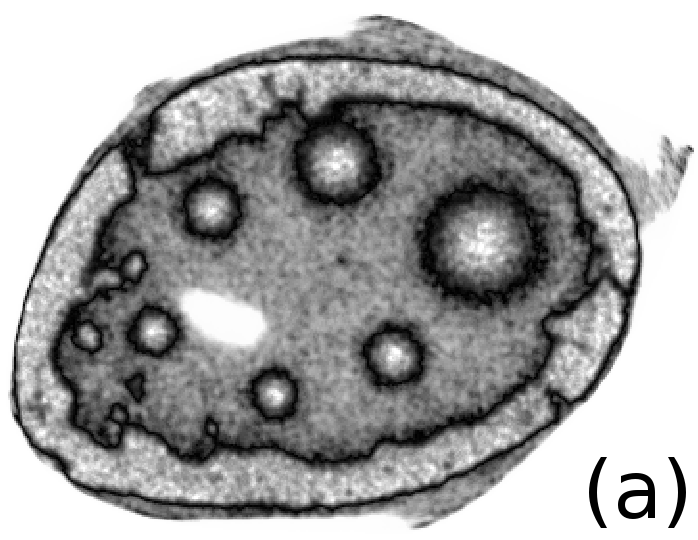

Reconstructed images are presented in Fig. 4. Since CGLS-TV- reconstruction might look more appealing than CGLS-EL we also show the surface representations of reconstructed images (see Fig. 5) and horizontal middle cross-sections (see Fig. 6).

One can notice that CGLS reconstruction is very noisy. CGLS-TV method better suppresses noise, however smooth features are strongly affected by the “staircasing” effect. CGLS-TV- method provides reconstruction with smoother features and CGLS-EL method resolves smooth features even better (e.g. cone-shaped parabola). Although CGLS-EL method performs very well for smooth objects one can notice the wave-like variations of intensity in the background and also at the top of the rectangle (see Fig. 6). This issue can be explained by the properties of our regularizer, in contrast to TV, our penalty does not seek the sparsest solution and does not penalize strongly (pushing to the constant value) a small intensity perturbations. The EL term tends to preserve all sharp edges while uniform noise is smoothed isotropically with the Laplacian. In Fig. 6 one can see that the CGLS-EL method provides better recovery of smooth features while slightly higher (compare to TV and TV-) perturbations visible in uniform areas (the top of the rectangle), however, the edges of the rectangle are defined sharper with the EL penalty.

In Fig. 10 and 11 one can notice that the BR is very smooth for TV and TV- penalties and some long-wave oscillations can be seen in the reconstructed image with EL penalty. This result corresponds to the expected behaviour of the EL penalty. We note here that the phantoms background (see Fig. 7) is not as flat as TV and TV- penalty recovered it. Furthermore, a small size dot-like feature (approximately in the centre of the phantom) is almost smoothed out with TV and TV- recovery. However, it is visible and well recovered with EL penalty. The sharp features, overall, are reconstructed very well with MLEM-EL method and seem even sharper compare to other methods (see the bone outer rim in Fig 10).